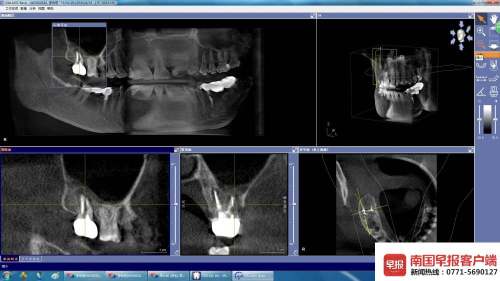

拍片显示的牙冠(白色)。

拍片显示的牙冠。

4月20日,广西医科大学附属口腔医院牙体牙髓科诊断为“慢性根尖周炎、慢性牙周炎”,治疗计划为方案一:根尖手术;方案二:拆除冠部修复后行根管再治疗。“后续治疗非常麻烦,不但要手术,还要植骨,况且费用也很高。”

天使口腔病历显示,2016年9月6日,李女士诉曾在别处进行嵌体修复,反复脱落。X片显示根充完善,诊断为残冠。当年9月21日,在局麻下,医生为李女士切龈,牙冠延长,备牙取模,拟国产氧化锆冠。